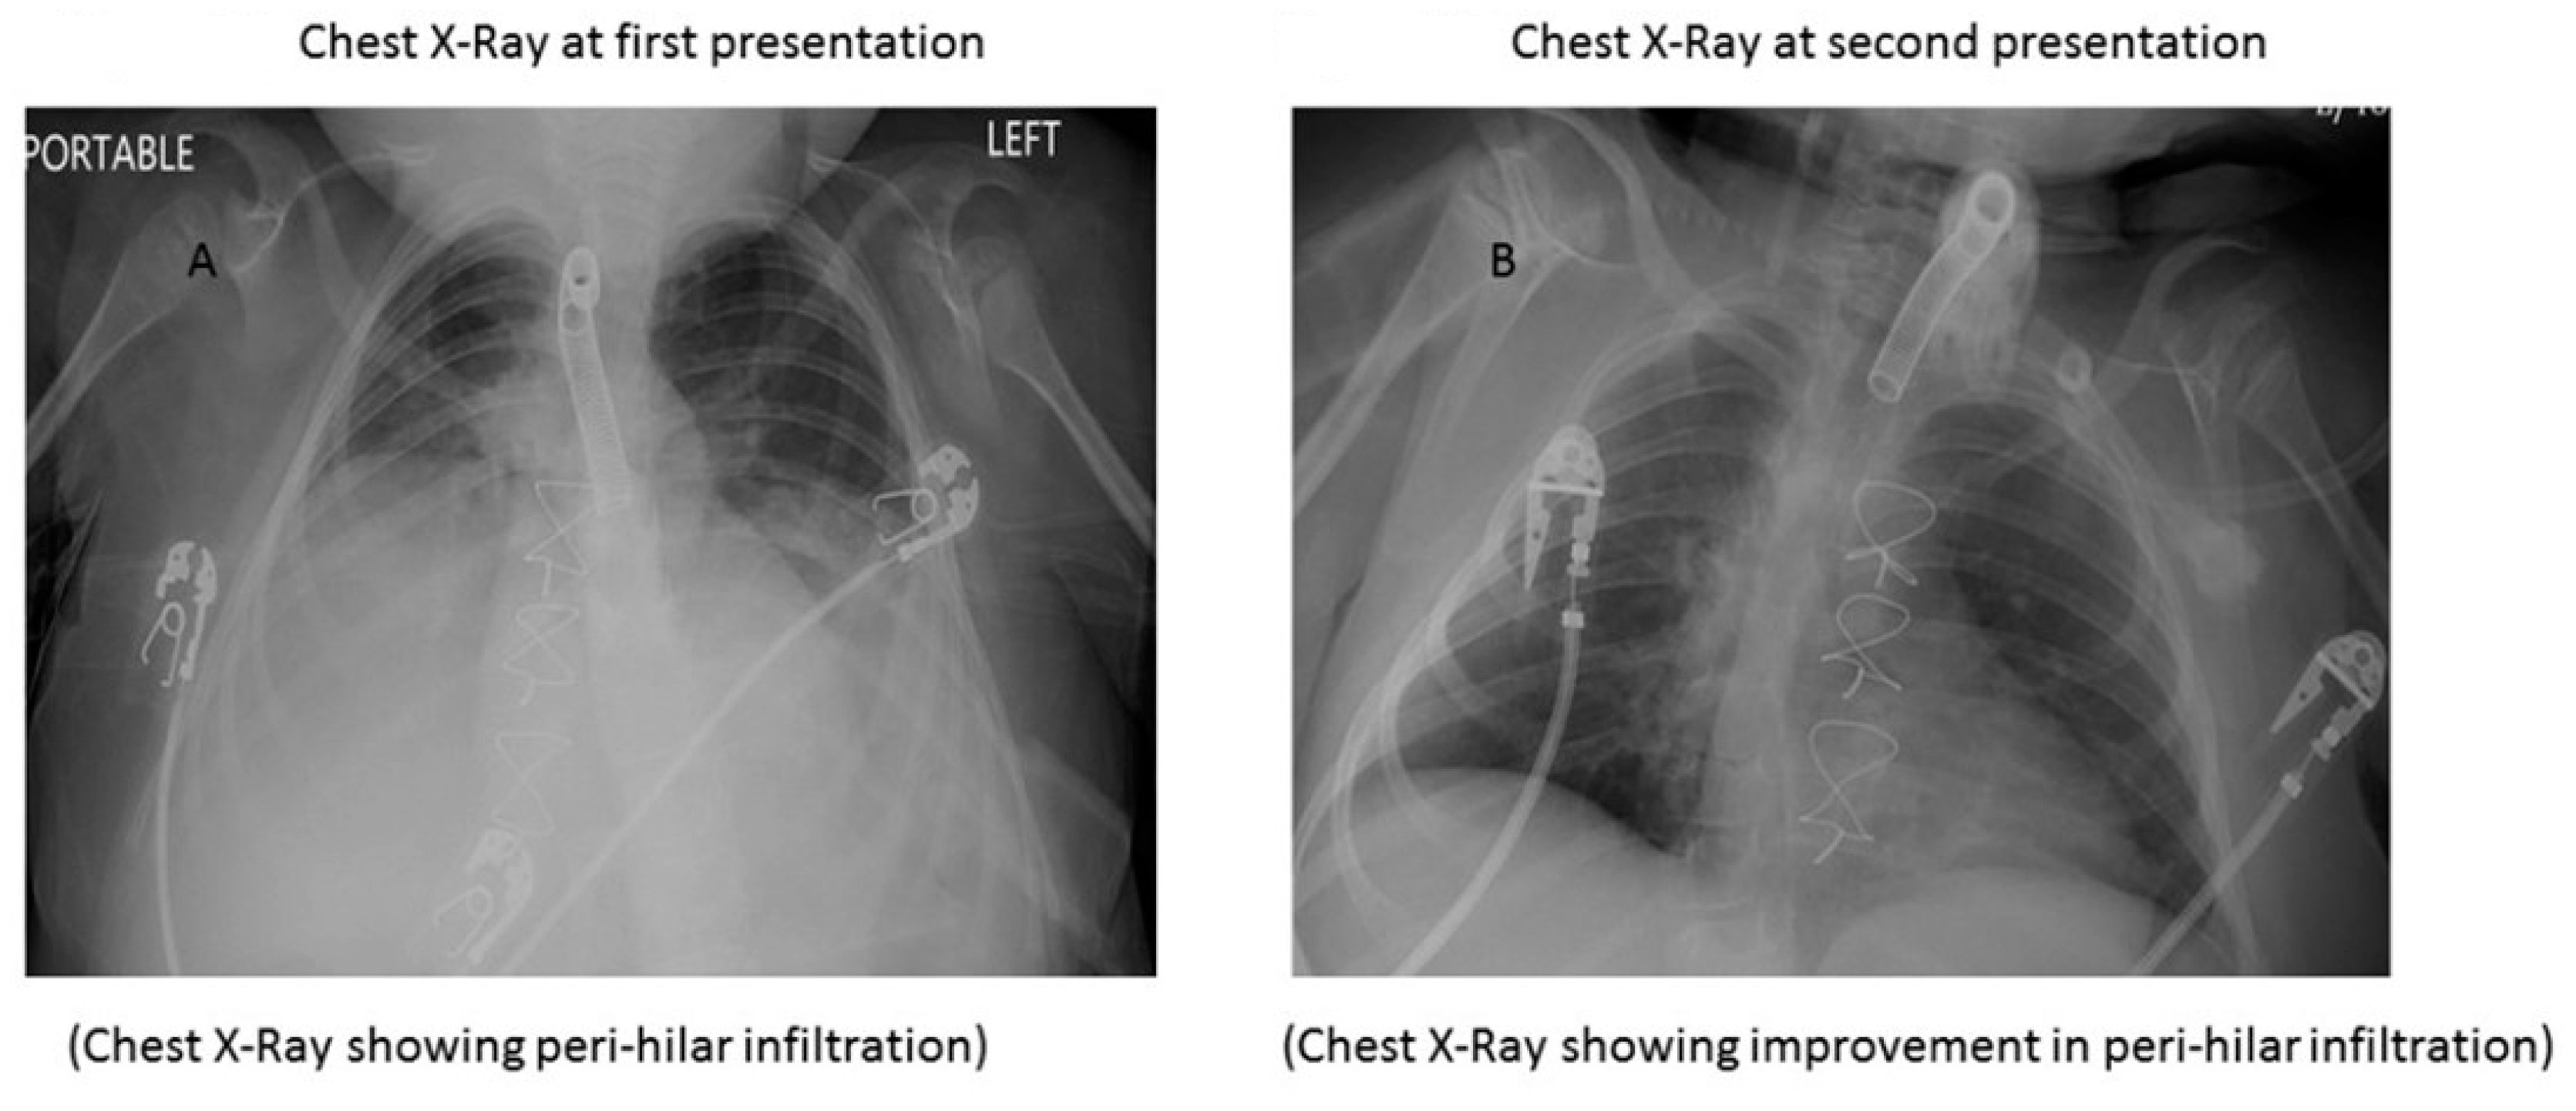

2. Case Report